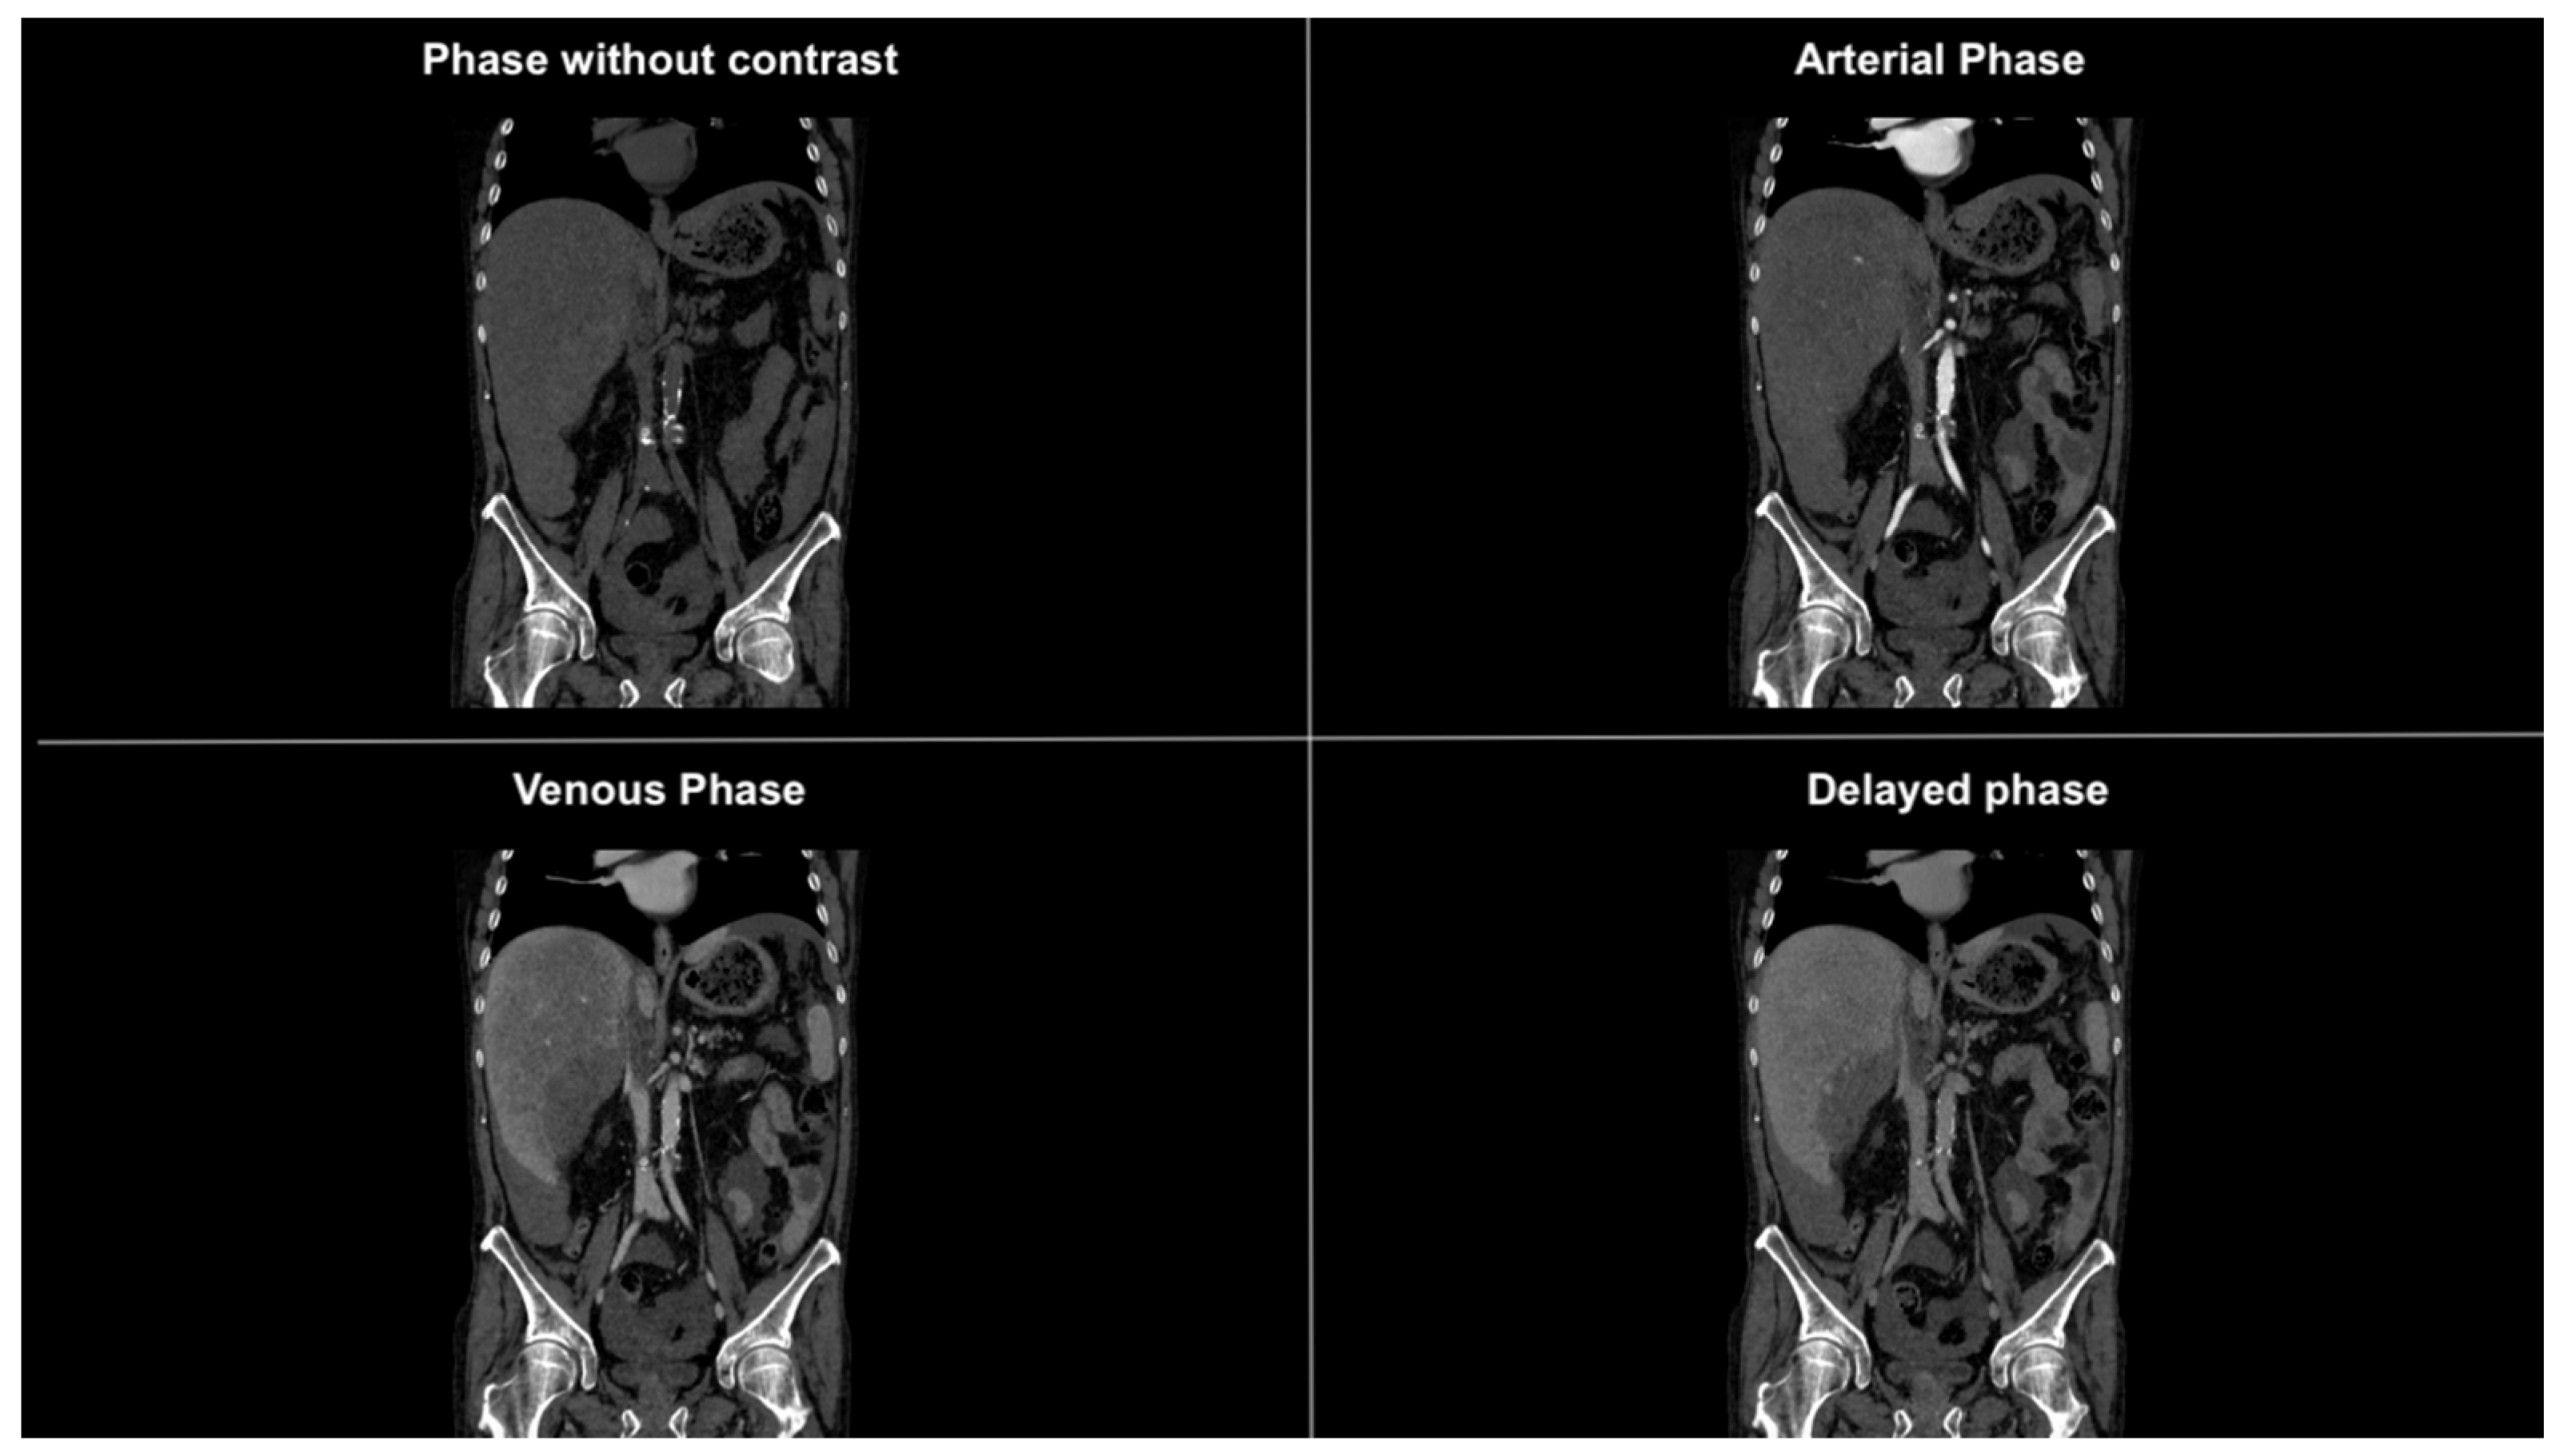

Figure 2. Coronal CT images in different phases showing subdiaphragmatic fluid collection bilaterally, within the paracolic gutters, and prominently around the liver. The fluid collection is suggestive of hemoperitoneum.